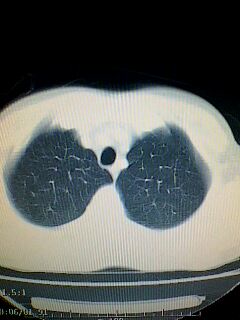

标题: CT28315:咳嗽咳痰咯血半月并胸痛 [打印本页]

标题: CT28315:咳嗽咳痰咯血半月并胸痛

图像资料欠清,建议强化,考虑周围型肺癌。

图像资料欠清,建议强化,考虑周围型肺癌。---支持